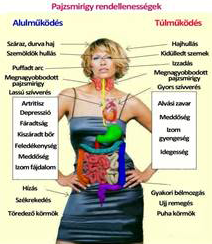

• Pajzsmirigy hormonok és vizsgálatuk. Alul működése okozta betegségek. Gyógyszeres és alternatív kezelése.

• Alulműködő pajzsmirigy oka, vizsgálata, kezelése. Főleg a nők betegsége

• Osteoren. Alulműködő pajzsmirigy és kezelése. Vérnyomás. Válasz 52

• Alul működő pajzsmirigy /Kurkumin / Lúgos víz fogyasztása /Gyógyszerek kapszula anyaga / Protonpumpa (PPI) gátló és aszpirin együttes szedése. A szervezetünk oxigén tartalmának növelése - Válasz 107